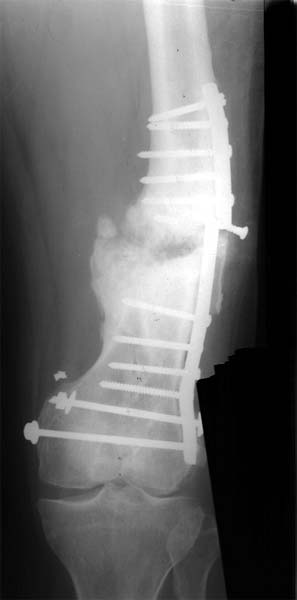

股骨远端骨折术后10年,4次手术均失败。经带锁髓内钉内 固定、植骨,骨生长因子和骨髓细胞注射,成功治愈